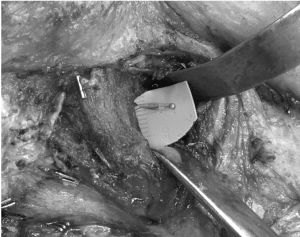

Following a discussion with the multidisciplinary tumor board, a right radical parotidectomy, ipsilateral selective neck dissection (levels II/III and VA) with possible temporal bone resection, facial nerve sacrifice and nerve grafting was recommended. During the procedure, frozen section pathology confirmed invasion of the facial nerve at the level of the stylomastoid foramen (Figure 3). As such, the facial nerve was sacrificed and removed en bloc with the tumor. Temporal bone resection was performed with frozen sectioning of the proximal facial nerve to confirm a negative margin and to have a proximal stump for nerve grafting (Figure 4). Nerve grafting was completed as planned with ansa cervicalis to marginal mandibular branch, masseteric nerve to zygomatic branch and facial nerve mastoid stump to the upper branches of the facial nerve using a cable graft from the nerve to vastus lateralis (Figure 5). The defect was reconstructed with a left anterolateral thigh free flap for volume restoration/coverage and a gold weight was inserted into the upper eyelid to enable eyelid closure.

Figure 5. Dissection of distal masseteric nerve through fibres of masseter prior to primary neurorrhaphy to the zygomatic branch of facial nerve